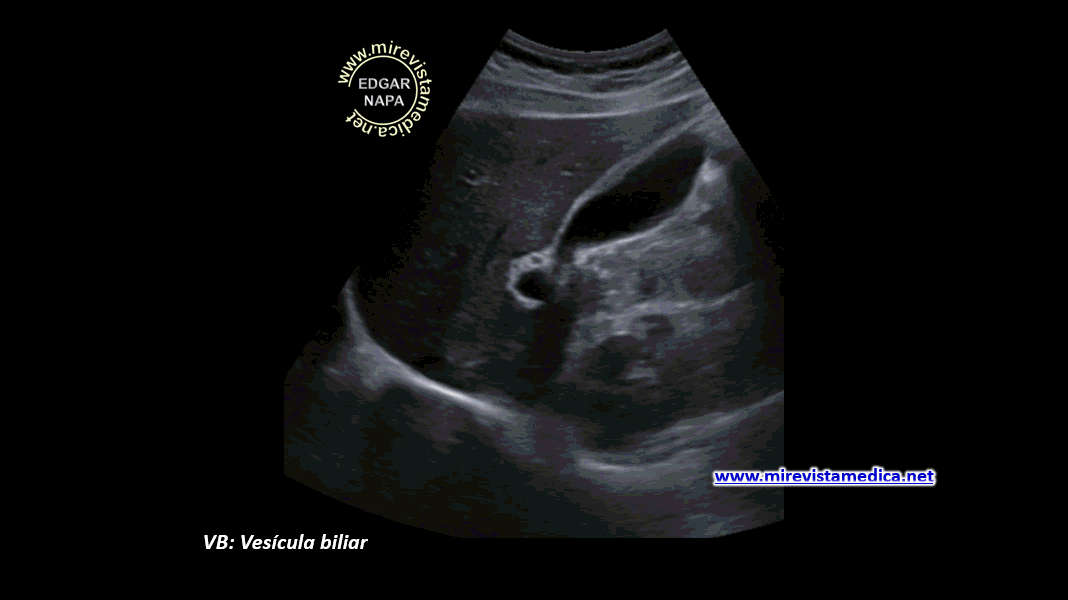

Vesícula en porcelana

La calcificación completa o parcial de la pared vesicular tiene su importancia al ser considerada como una lesión premaligna por lo que requiere un Tratamiento quirúrgico.

Es la Rx simple de abdomen la que establece el diagnosico detectando un área calcificada a nivel vesicular, siendo necesario su confirmación por US.

Este hallazgo representa una alta incidencia de carcinoma ( hasta el 60% de los casos ).